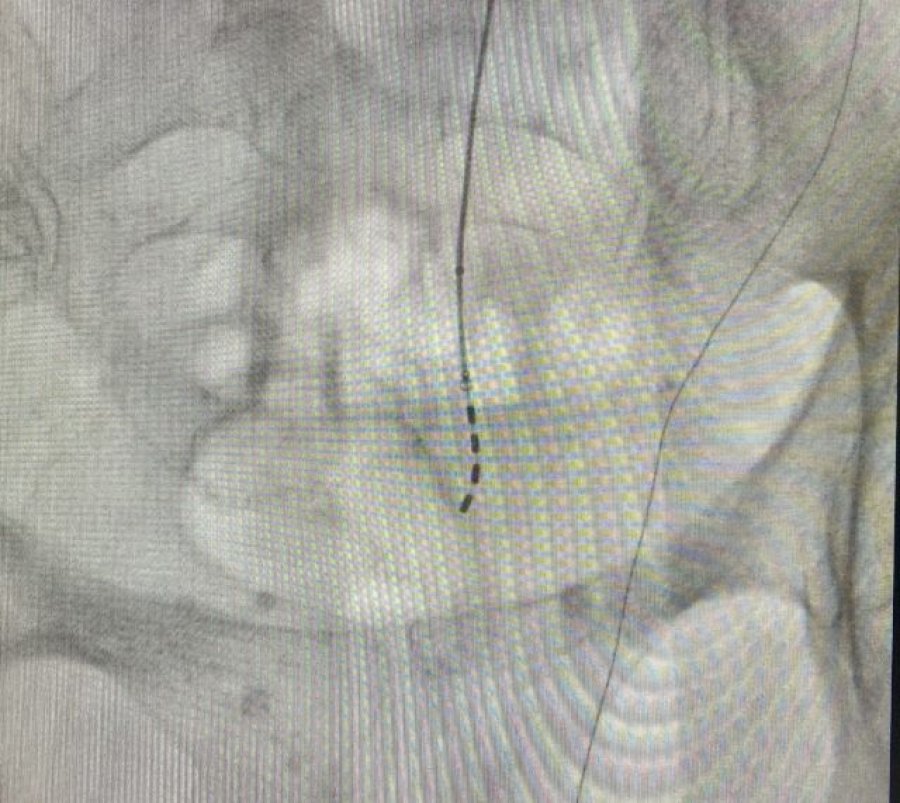

Se trata de una técnica mínimamente invasiva que consiste en la colocación de un electrodo sobre los nervios sacros encargados de transmitir las señales neurológicas que permiten el control de la evacuación urinaria y fecal. El dispositivo se implanta con anestesia local, sedación ligera y control radiológico. Su colocación no requiere ingreso hospitalario, de forma que el paciente recibe el alta apenas unas horas después del procedimiento.

Según explica Domínguez, la intervención se realiza en dos fases. En la primera, se coloca el electrodo sobre el nervio sacro y se conecta a una batería externa pegada a la piel mediante unos apósitos. De esta manera y durante unos días, como periodo de prueba, el paciente tiene la posibilidad de comprobar la eficacia del dispositivo en su domicilio, mediante la reducción de los episodios de incontinencia. Una vez se comprueba la mejoría clínica y se confirma que la terapia es adecuada, se realiza la segunda fase del procedimiento mediante la cual el electrodo se conecta a un generador subcutáneo de reducido tamaño.